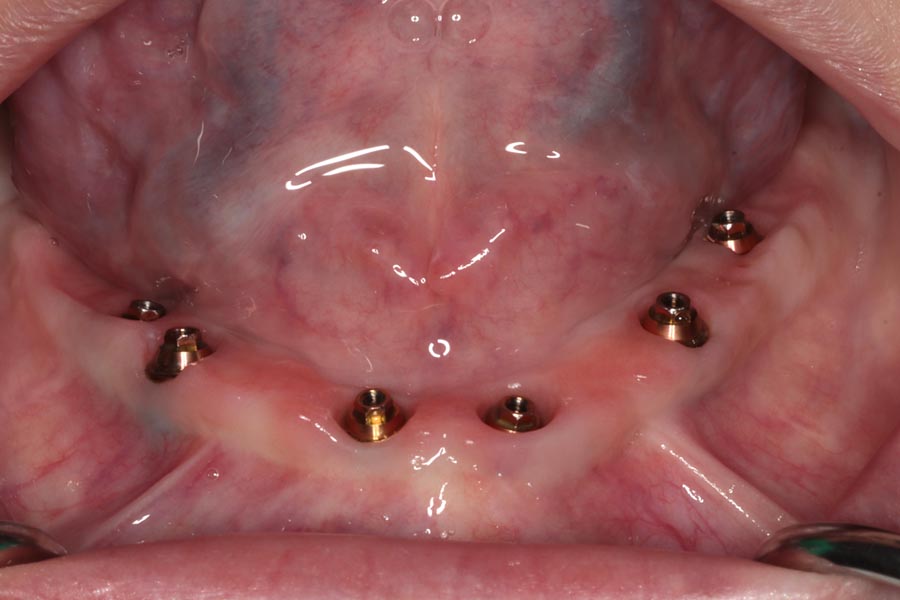

On the day of delivery, tissues are pink and healthy. The provisionals have helped to shape them perfectly to prepare them for the definitive restorations.